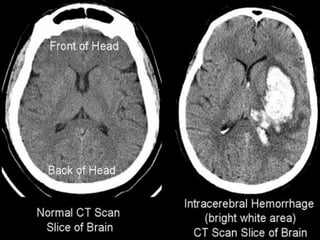

• Hyperdense : apparait plus dense que son

environnement

• Hypodense : densité plus faible

• Isodense : densité similaire

• Hyperdensite spontanée : sur un examen sans

injection de produit de contrast uniquement

Traduit le plus souvent un saignement récent

Calcifications

HEMATOMES

INTRAPARENCHYMATEUX